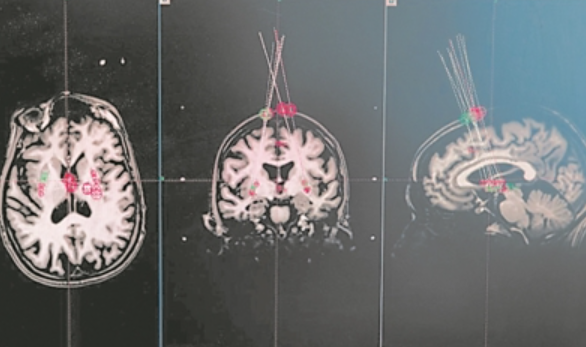

瑞典斯科訥大學(xué)醫(yī)院科學(xué)家利用一根針頭,將細(xì)胞移植到人腦中,以治療帕金森病。圖片來源:英國《自然》網(wǎng)站

科學(xué)家根據(jù)腦部MRI掃描圖像確定針頭將細(xì)胞送往何處。圖片來源:英國《自然》網(wǎng)站